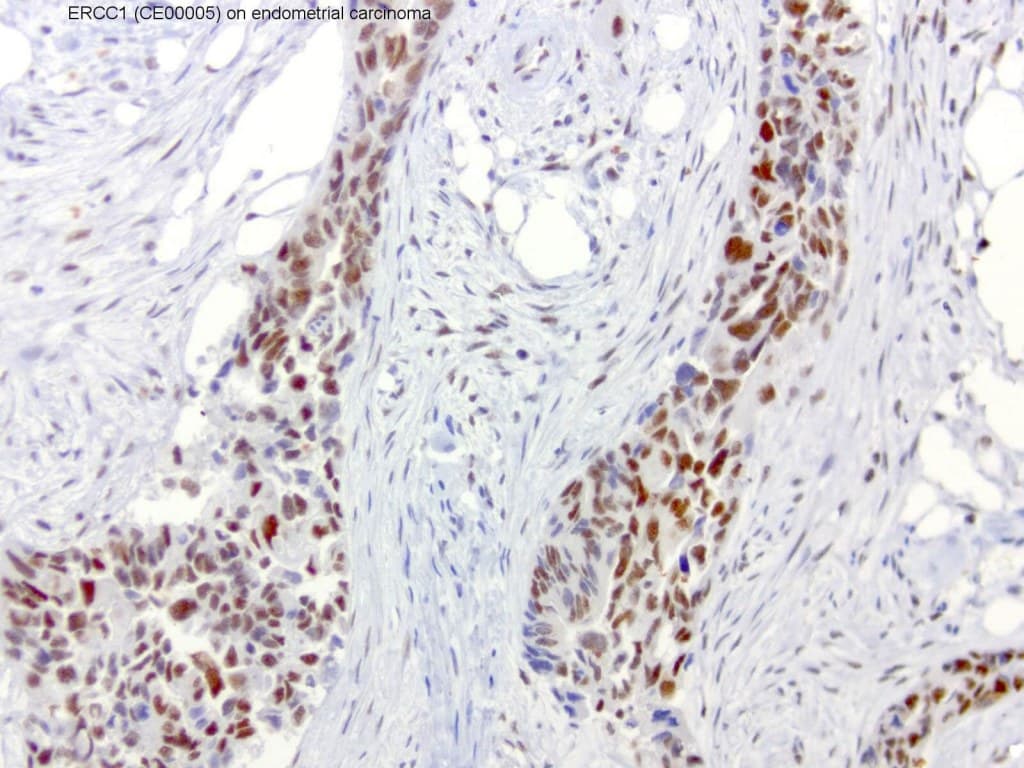

Secção de carcinoma endometrial